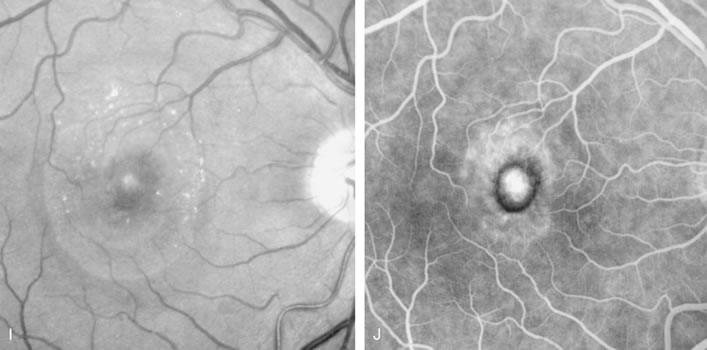

Conventional laser thermophotocoagulation is the treatment of choice for extrafoveal, well-defined, classic CNV. Photodynamic treatment (PDT) is the treatment of choice for subfoveal, predominantly classic CNV. FA is used to localize the lesion in relation to the fovea, classify the subtype, choose the type of procedure, and guide the treatment (Figs. 18, 19, and 20).56–73

Fig. 18. A. Late-phase fluorescein angiogram demonstrates the presence of actively leaking, subfoveal, classic choroidal neovascularization. B. After photodynamic treatment (PDT) with Visudyne there was complete closure of the neovascular membrane. The round, hypofluorescence corresponds to the area treated with PDT. There was no damage to the retinal vasculature.

Fig. 19. A. Red-free photograph of the right eye of a patient with exudative angiomatous macular degeneration. B. Fluorescein angiography reveals the presence of subfoveal, classic choroidal neovascularization (CNV). The boundaries of the CNV are digitally traced (yellow), and the greater linear dimension of the lesion is measured (red) to guide the PDT.

Fig. 20. A. Red-free photograph of a 20-year-old patient with sudden loss of vision to the level of 20/200. There is exudative, neurosensory macular detachment, a few hemorrhages, and lipid exudates. B. Fluorescein angiography reveals the presence of classic choroidal neovascularization (CNV), which appears to be juxtafoveal (<200 μ from fixation). Given the size of the CNV and its proximity to the fovea, it was decided to treat the patient with photodynamic treatment (PDT). C. Red-free photograph of the same eye 2 weeks after PDT; there is increased subretinal exudation D. Fluorescein angiography demonstrates that the CNV is still actively leaking. E. Red-free photograph 4 weeks after PDT demonstrates further increase in the size of the neurosensory macular detachment, subretinal hemorrhages, and lipid exudation. F. Fluorescin angiography reveals that the CNV has extended under the fovea. Given the young age of the patient, an inflammatory component of the neovascular process was suspected. It was decided to give a posterior, subtenon injection of triamcinolone acetonide, 40 mg/1 mL. G. Two weeks after steroid treatment there is partial reabsorption of the subretinal fluid. H. Fluorescein angiography demonstrates contraction of the CNV. I. Four weeks after injection of triamcinolone there is further reduction in the degree of neurosensory detachment; vision had improved to 20/60. J. Fluorescein angiography demonstrates that the CNV is smaller and less active (less leakage).